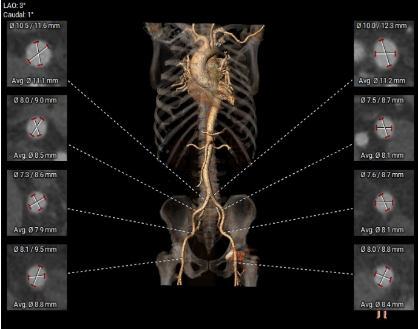

血管三维重建